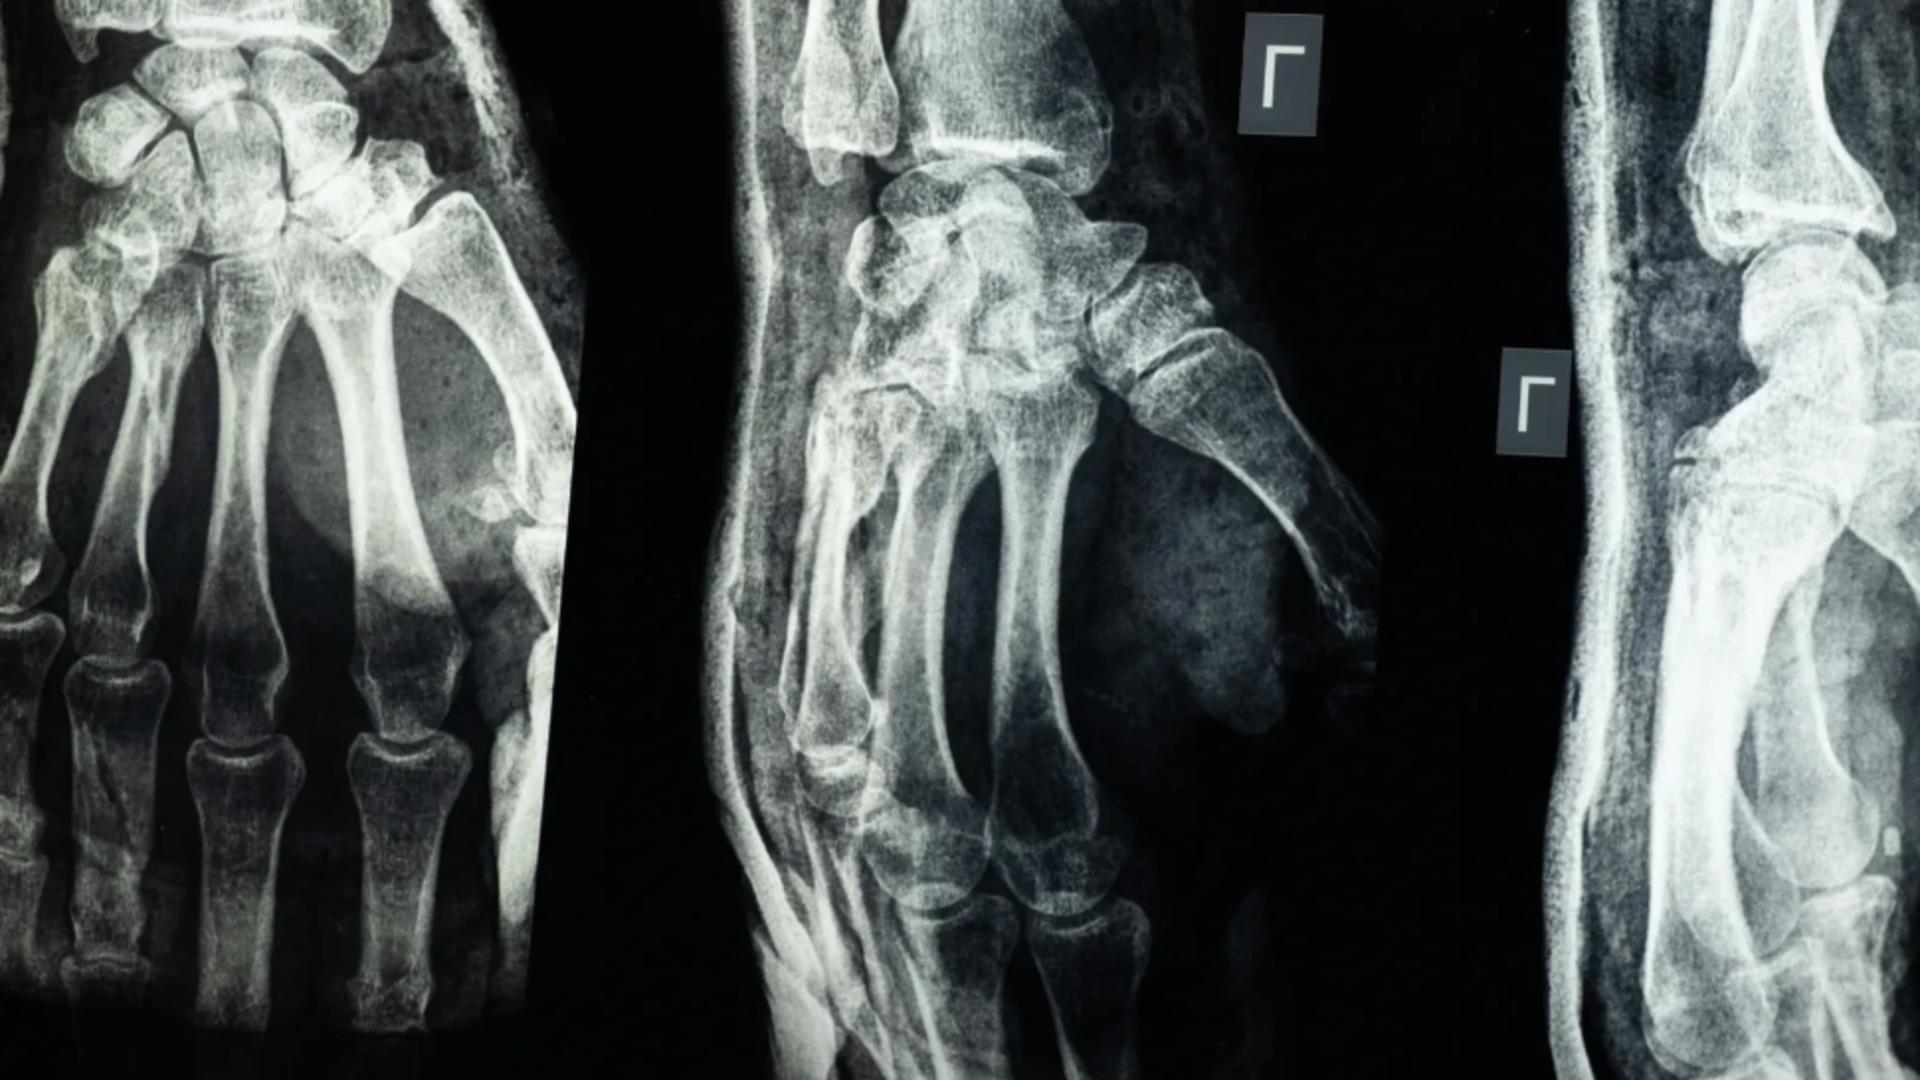

O echipă de cercetători din provincia Zhejiang, China, a creat un adeziv medical capabil să repare fracturile osoase în numai 2-3 minute.

Produsul, denumit „Bone-02”, are potențialul de a înlocui implanturile metalice folosite în prezent și de a reduce drastic perioada de recuperare a pacienților.

Noul adeziv are două caracteristici cheie: fixează rapid osul și se absoarbe treptat în organism pe măsură ce acesta se vindecă. În acest fel, pacienții nu mai au nevoie de o intervenție suplimentară pentru îndepărtarea implanturilor, scrie ndtv.

Testele de laborator, urmate de studii clinice pe mai mult de 150 de pacienți, au demonstrat că „Bone-02” oferă o rezistență similară cu cea a implanturilor metalice. Forța de lipire depășește 400 de livre, iar rezistența la compresiune se ridică la aproximativ 10 MPa.